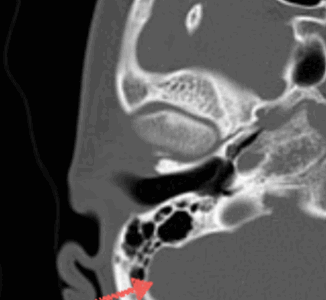

Также при компьютерной томографии височной кости есть возможность выявить изменения внутренней сонной артерии так, как визуализируется канал сонной артерии, который расположен кпереди от ямки яремной вены. Канал артерии меньше канала вены, поэтому радиологи всегда могут отличить их друг от друга. Стрелкой указан угол сигмовидный синус. Важный критерий диагностики при инфекционных заболеваниях среднего уха, головы и шеи .В данном месте часто встречается тромбоз. Также КТ внутреннего уха выполняют для оценки воздушности сосцевидного отростка, что особенно важно у пациентов с тугоухостью, которая вызвана, как первичными, так и вторичными причинами. Если вы сомневаетесь в правильности вашего диагноза по поводу заболеваний слухового аппарата, вы всегда можете заказать услугу второго мнения по вашим снимкам, заключениям из истории болезни, анализам.

МСКТ височной кости — КТ-картина образования пирамиды правой височной кости с костно-деструктивными изменениями, правостороннего среднего отита. Образование на МСКТ височной кости отграничено сверху базальным завитком улитки и преддверием, снизу — яремной веной, медиально — твердой мозговой оболочкой задней черепной ямки, латерально — гипо- и мезотимпанумом, спереди — вертикальной частью внутренней сонной артерии, сзади — сагиттальным ПК, внутренним слуховым проходом (рис. 1). Рис. 1. МСКТ височной кости (правое ухо). КТ-картина инфралабиринтной холестеатомы пирамиды височной кости (а — аксиальная проекция, б — коронарная проекция).